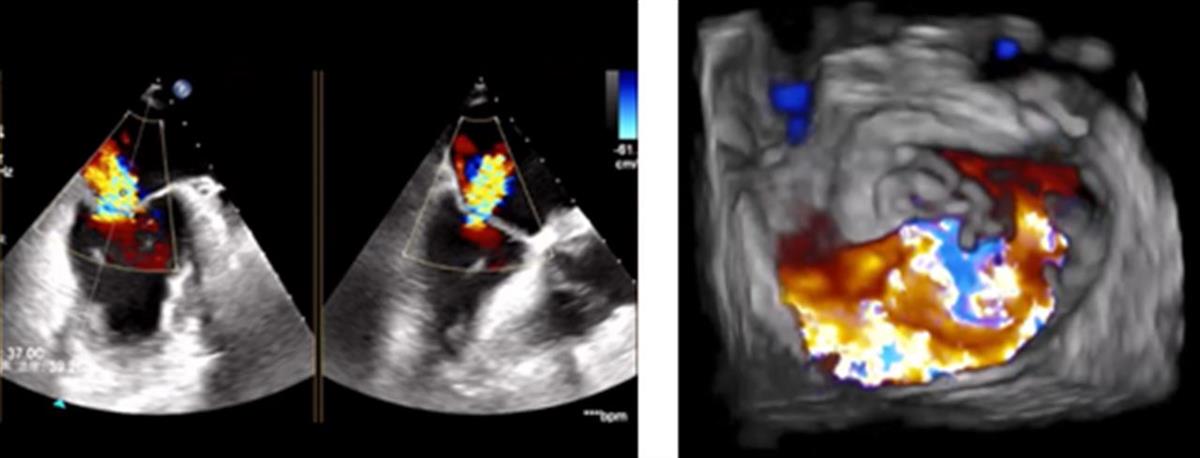

近期,80岁的胡奶奶夜间睡觉犯了难,常出现阵发性呼吸困难、无法平卧、双下肢水肿等症状,多次外院治疗后效果欠佳,转入武汉大学人民医院心血管医院心脏特需医疗科。完善食管超声心动图评估提示:二尖瓣重度关闭不全,合并双房大、升主动脉扩张及主动脉瓣轻-中度关闭不全。

84岁杨奶奶也长期受夜间阵发性呼吸困难困扰,就诊于外院行药物治疗后效果欠佳,走投无路的她求助于武汉大学人民医院心血管医院心脏特需医疗科。完善相关检查后提示:二尖瓣前瓣脱垂致重度关闭不全,合并肺动脉压轻度升高。

胡奶奶(左图)、杨奶奶(右图)术前心超提示二尖瓣重度关闭不全